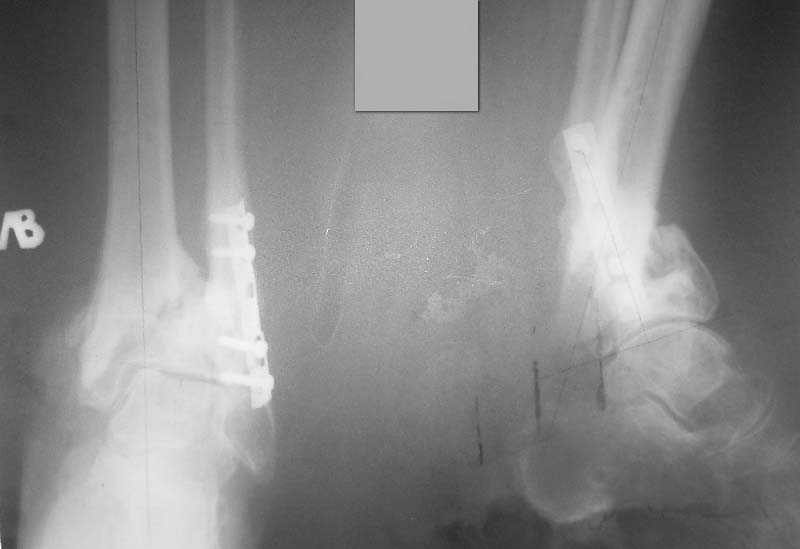

Уважаемые коллеги! Интересно ваше мнение по тактике лечения данной пациентки.Женщина 72 л соматически сохранная, умеренно полная, в мае прошлого года получила бытовую травму - открытый оскольчатый внутрисуставной перелом дистального метаэпифиза большеберцовой кости (Gustilo III-A) и поперечный перелом н/з малоберцовой кости со смещением отломков. Оперирована ургентно - открытая репозиция отломков малоберцовой кости, остеосинтез пластиной. ПХО раны голеностопного сустава, стабилизация отломков большеберцовой кости стержневым аппаратом. Репозиция отломков удовлетворительная (варус до 5 гр, рекурвация до 5 гр) - сильно за ней не гонялись, много осколков. В дальнейшем заживление ран первичное. Аппарат до 3 мес, затем гипсовая лонгета. Общий срок иммобилизации и разгрузки нижней конечности 4,5 мес - разрешена нагрузка после клинических и рентгенологических? признаков сращения. Последние 4 мес из поля зрения выпала, появилась сегодня. Беспокоят сильные боли при ходьбе, деформация голени, хромота. Р-контроль прилагается - варус 16 гр, рекурвация 35 гр (прошу прощения за качество снимков). Клинически варусно-рекурвационная деформация н/з голени, подвижность в н/з, боль. Движения в голеностопном суставе разгибание-сгибание 0/0/20. Трофика не нарушена, рубец области медиальной лодыжки плотный, спаян с подлежащими тканями. Больная хочет ходить без боли на ровной ноге (что вполне естественно). Возникает вопрос - как этого добиться? Удаление металлоконструкций, остеотомия малоберцовой на мой взгляд не обсуждаются - выполняются при любом из выбранных методов лечения (далее как мне видится в порядке предпочтения): - коррекция деформации аппаратом Илизарова с последующим БИОС ретроградным стержнем типа T2 AAN или аналогами (читал за и против данного метода, но по моему он единственный обеспечит больной раннюю нагрузку и стабильность пусть даже ценой потери ГСС (который и так уже потерян ИМХО) и ПТС). -коррекция деформации аппаратом Илизарова с оставлением этой фиксации как окончательной (необходимо ли выполнение свободной костной пластики). -открытая репозиция, остеосинтез LCP с костной пластикой. Данный метод на мой взгляд не позволит добиться хорошей стабильности, учитывая небольшой дистальный отломок и пороз кости (уже при первой операции обращала на себя "пустота" метаэпифиза), будет сопряжен с дополнительной иммобилизацией, как следствием потерей функции голеностопного сустава, невозможностью ранней нагрузки конечности. Кроме того, наиболее травматичное вмешательство, а м/ткани этой области скомпрометированы первичной травмой - как пойдет заживление. Таково мое видение проблемы. Женщине очень хочется помочь, поэтому буду рад выслушать все мнения, доводы "за" и "против" какого-то метода, другую тактику.